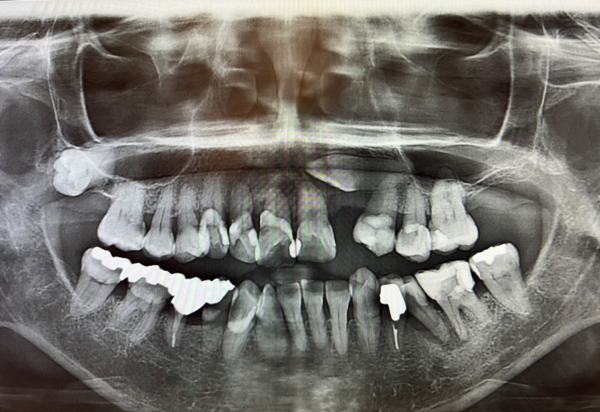

エックス線写真を撮影すると、八重歯が顎の骨の中に埋まっており、左上の奥歯を抜いたところは骨も非常に薄いことがわかりました。このように、埋伏した歯がある場合や、骨が非常に薄い場合、インプラントでの修復は困難であるため、入れ歯での修復が適正であると伝えたところ、違和感の少ない入れ歯での治療を希望されました。